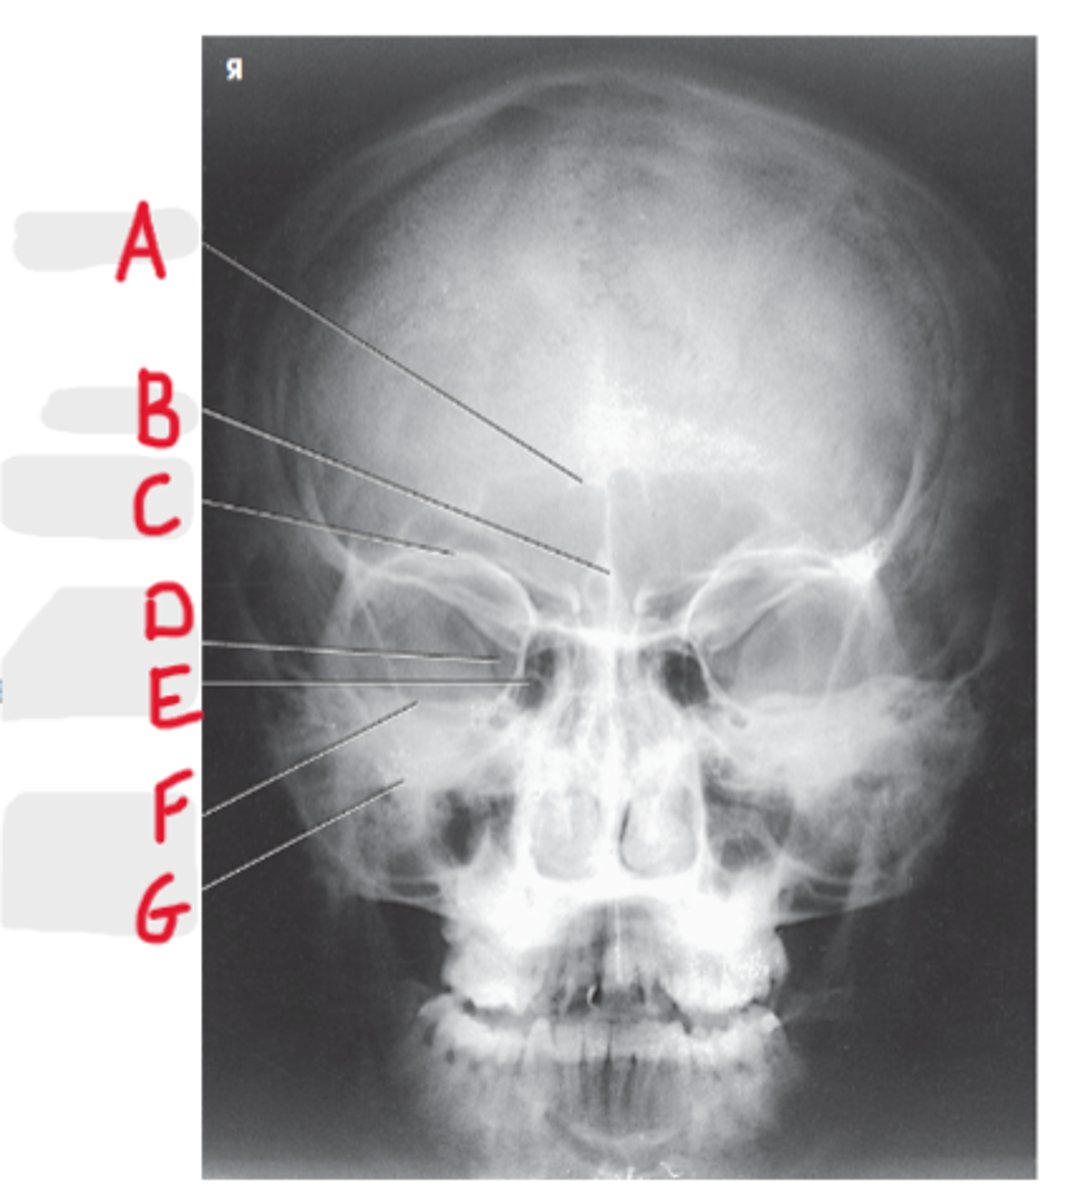

PA Skull

What projection is this?

Orbits fill the petrous ridges

How can we tell this is a PA skull?

CR to exit the nasion

What is the CR for a PA or PA axial (Caldwell) skull?

OML perpendicular to IR

What line should be perpendicular to the IR for a PA or PA axial (Caldwell) skull?

Frontal sinus

A

Crista galli

B

Superior orbital margin

C

Superior orbital fissure

D

Ethmoid sinus

E

Petrous ridge

F